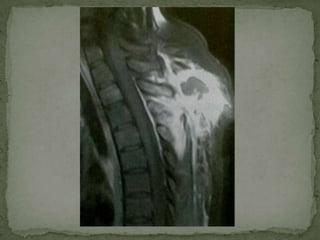

Cord edema

Thinning &

stretching of

the cord